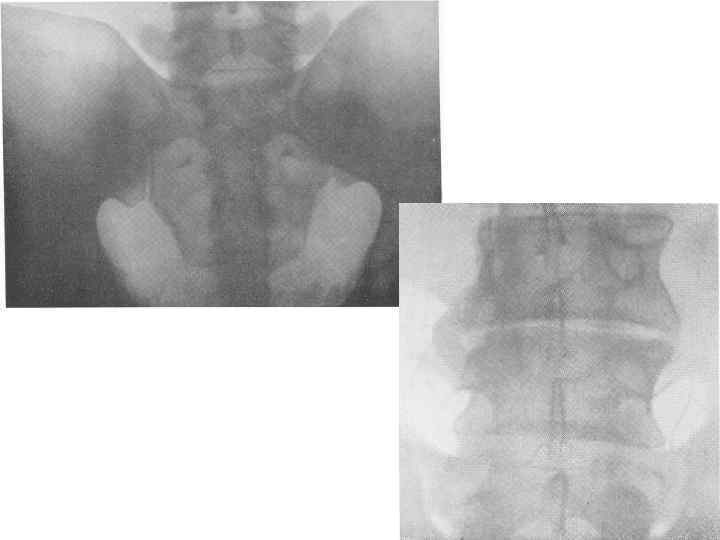

Рентгенографические признаки • Сакроилеит: • В костном массиве ушковидного отростка одной из костей теряется правильный губчатый структурный рисунок, • появляются один или несколько округлых небольших, до 8— 10 мм в окружности, деструктивных очагов, обычно сливающихся друг с другом. • Контуры подвздошной кости и крестца становятся вместо четких изъеденными, изгрызанными. • Из-за разрушения хрящевых прослоек сочленения суставная щель постепенно суживается, а в дальнейшем наступает очень часто полный костный анкилоз, с переходом трабекулярного рисунка с одной кости непосредственно на другую. • Секвестрация наступает очень редко. • В окружности деструктивных очагов виден реактивный воспалительный грубопятнистый остеосклероз.

Рентгенографические признаки • Сакроилеит: • В костном массиве ушковидного отростка одной из костей теряется правильный губчатый структурный рисунок, • появляются один или несколько округлых небольших, до 8— 10 мм в окружности, деструктивных очагов, обычно сливающихся друг с другом. • Контуры подвздошной кости и крестца становятся вместо четких изъеденными, изгрызанными. • Из-за разрушения хрящевых прослоек сочленения суставная щель постепенно суживается, а в дальнейшем наступает очень часто полный костный анкилоз, с переходом трабекулярного рисунка с одной кости непосредственно на другую. • Секвестрация наступает очень редко. • В окружности деструктивных очагов виден реактивный воспалительный грубопятнистый остеосклероз.